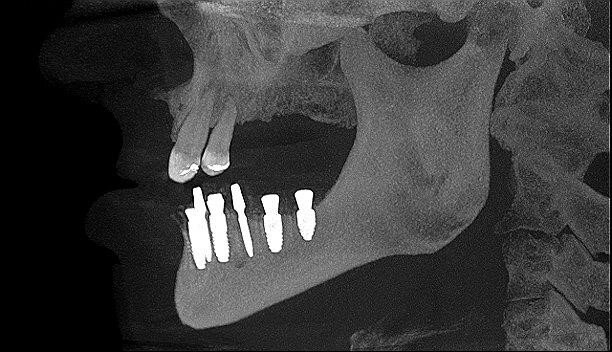

Wykonano CBCT, z którego wynikało, iż pacjent ma chorobę przyzębia. Zakwalifikowano wszystkie 10 zębów żuchwy do ekstrakcji. Zaplanowano zaopatrzenie pacjenta 8 implantami ICX oraz 5 implantami tymczasowymi Alpha Bio w celu wykonania pracy protetycznej tymczasowej bez obciążenia implantów docelowych ze względu na brak kontroli nad pacjentem w okresie wgajania implantów (zdjęcie CBCT oraz wewnątrzustne pacjenta). Za pomocą komputerowego systemu nawigacyjnego 3D został zaprojektowany szablon przytwierdzany 3 pinami do kości żuchwy w celu jego stabilizacji.

Następnie przytwierdzono ponownie szynę i kolejnymi wiertłami zaopatrzonymi w stopery rozpoczęto preparację łoża dla implantów. Podczas pracy pozyskiwano kość własną pacjenta w celu późniejszej augmentacji. Po przygotowaniu wszystkich miejsc implantacyjnych przystąpiono do wprowadzenia wszystkich 8 implantów poprzez tuleje w szablonie, a następnie usunięto szablon z jamy ustnej pacjenta i założono śruby gojące. Kolejnym etapem pracy było wprowadzenie 5 implantów tymczasowych oraz zaopatrzenie zębodołów poekstrakcyjnych materiałem kostnym własnym pacjenta zmieszanym z materiałem ksenogennym i osoczem. Augmentat pokryto błonami PRF i zaszyto śluzówkę. Wprowadzono antybiotykoterapię. Wykonano zdjęcie CBCT kontrolne po zabiegu.